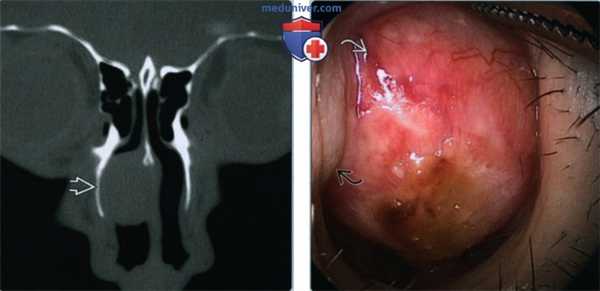

(Слева) При корональной костной КТ в полости носа справа определяется хорошо отграниченная ДСО, прилежащая к носовой перегородке. Определяется смещение кнаружи и ремоделирование латеральной стенки носа, типичное для доброкачественных процессов.

(Справа) На эндоскопической фотографии в передних отделах полости носа определяется хорошо отграниченная округлая ДСО, происходящая из передних отделов носовой перегородки.